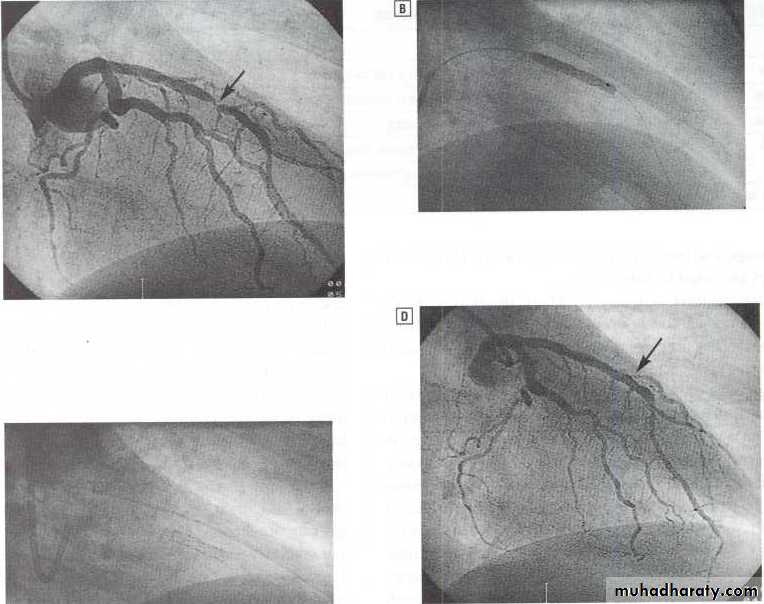

Percutaneous coronary intervention PCI.

Primary percutaneous coronary intervention (PCI).Thrombolysis.